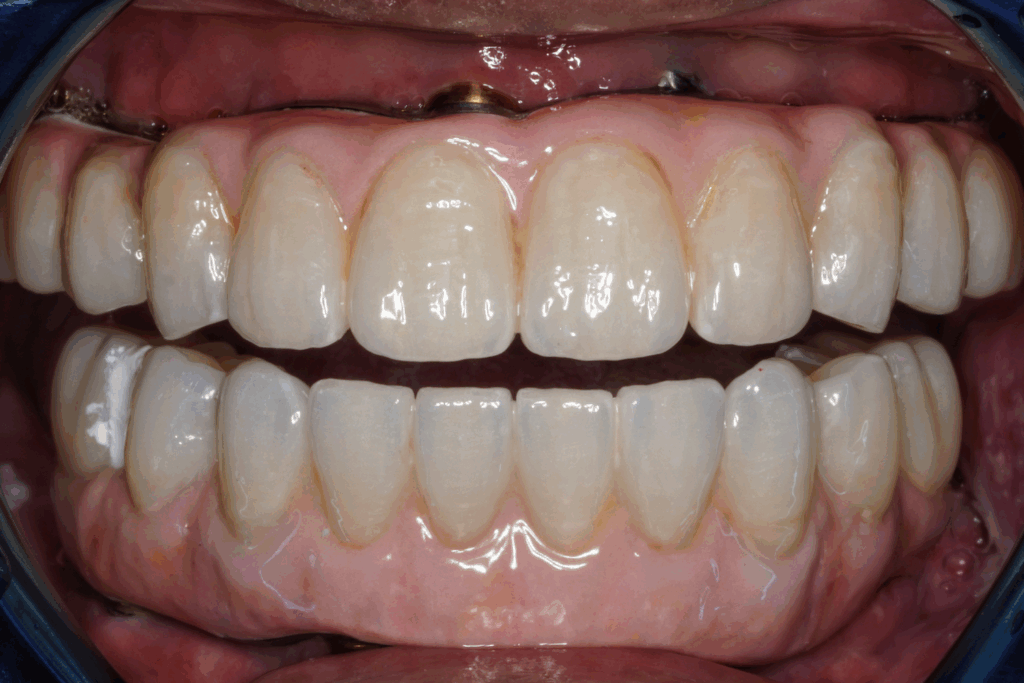

案例1. 上顎+下顎All on X

Before

After